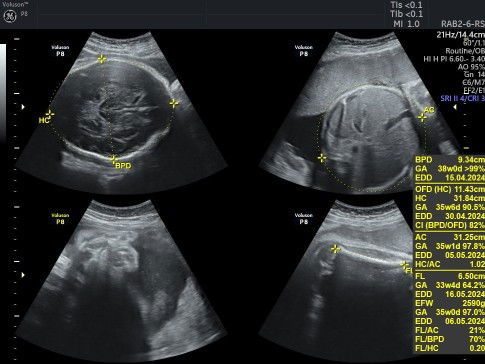

BPD janin lebih besar dari usia kehamilan

Halo bun. Kemarin saya usg di usia kehamilan 32w4d. Alhamdulillah kata dokter semua aman, struktur otaknya bagus banget, jantung, janin, dll insyaa Allah semua bagus. Cuma bbjnya yg kelebihan.. tapi sampe rumah overthinking bgt krn baru engeuh BPDnya besar banget, sampe selisih 5 mingguan. Kalau kaya gini aman gak yaa bun? Adakah bunda yg pernah mengalami hal serupa? Boleh sharingnya yaa bun krn ovt banget🥺 #SeriusTanya #ingintahu #bantusharing

Halo bun. Kemarin saya usg di usia kehamilan 32w4d. Alhamdulillah kata dokter semua aman, struktur otaknya bagus banget, jantung, janin, dll insyaa Allah semua bagus. Cuma bbjnya yg kelebihan.. tapi pas sampe rumah overthinking bgt krn baru engeuh BPDnya besar banget, sampe selisih 5 mingguan. Kalau kaya gini aman gak yaa bun? Adakah bunda yg pernah mengalami hal serupa? Boleh sharingnya yaa bun krn ovt banget🥺 #SeriusTanya #ingintahu #bantusharing